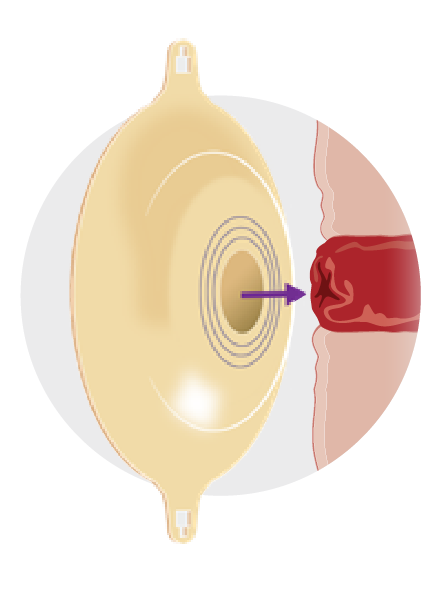

What is convexity?

Convexity is the outward curving of the wafer or skin barrier

The curved shape provides gentle pressure around the stoma to improve contact with the skin and help maintain a secure seal.1

Because every body is different, convex systems can support a wide range of stoma profiles by helping maintain a reliable seal.